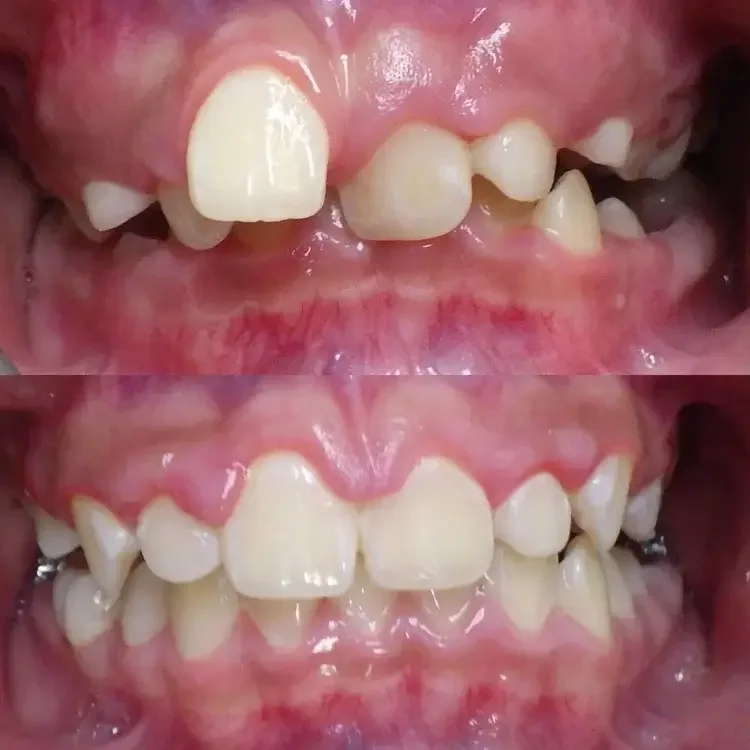

Before And After Kids Braces Results in Los Angeles